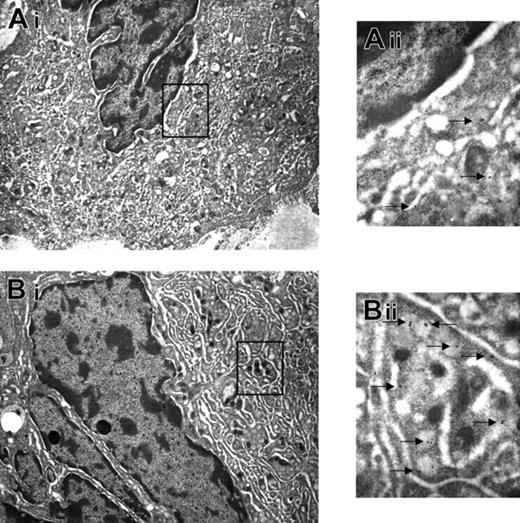

TPO treatment restored Mk maturation in GATA-1low mice. Immunoelectron microscopy for von Willebrand factor of Mks from the spleen of untreated GATA-1low mouse (A) and from a mutant mouse after 7 days of TPO treatment (B). The cytoplasm of the Mks from TPO-treated animals contains clearly recognizable platelet territories with numerous electron-dense granules, which, when analyzed at higher magnification, contain several von Willebrand factor–related gold particles (Bii). The rectangle in panels A and B indicates the region of the Mks shown at higher magnification in Aii and Bii, respectively. The arrows in Aii and Bii indicate von Willebrand factor–related gold particles. Magnification, × 4400 (Ai,Bi) and × 30 000 (Aii,Bii). Numerical aperture of the objective lenses: 0.1.

TPO treatment had profound effects on the morphology of Mks both in wild-type and GATA-1low mice. In wild-type mice, the overall morphology of the Mks in the spleen became less mature, as revealed by reduced localization of P-selectin (Schmitt et al32 and results not shown) and von Willebrand factor (Table 2) on the α-granules. In addition, a significant portion (31 ± 2.6%) of these Mks had the heavy-electron dense para-apoptotic morphology originally described for GATA-1low Mks22 and contained neutrophils embedded in the cytoplasm, as confirmed by myeloperoxidase immunostaining (Figure 4). In contrast, in TPO-treated GATA-1low mice, the morphology of the Mks became more mature with clearly delineated platelet territories and significant increase, both in number and in localization to the α-granules, of von Willebrand factor–related gold particles (Figure 5; Table 2). These stage III Mks, never detected in untreated mutants,22 represented 28.5% of the Mks in spleen from TPO-treated GATA-1low Mks.